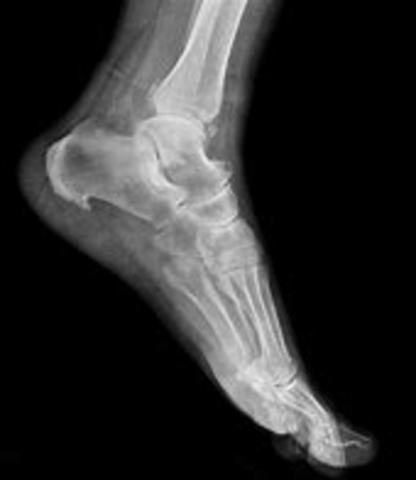

• Digital X-ray Introduced

Digital X-ray Introduced

The Digital X-ray was introduced to see what tendons and ligaments might be torn in the body